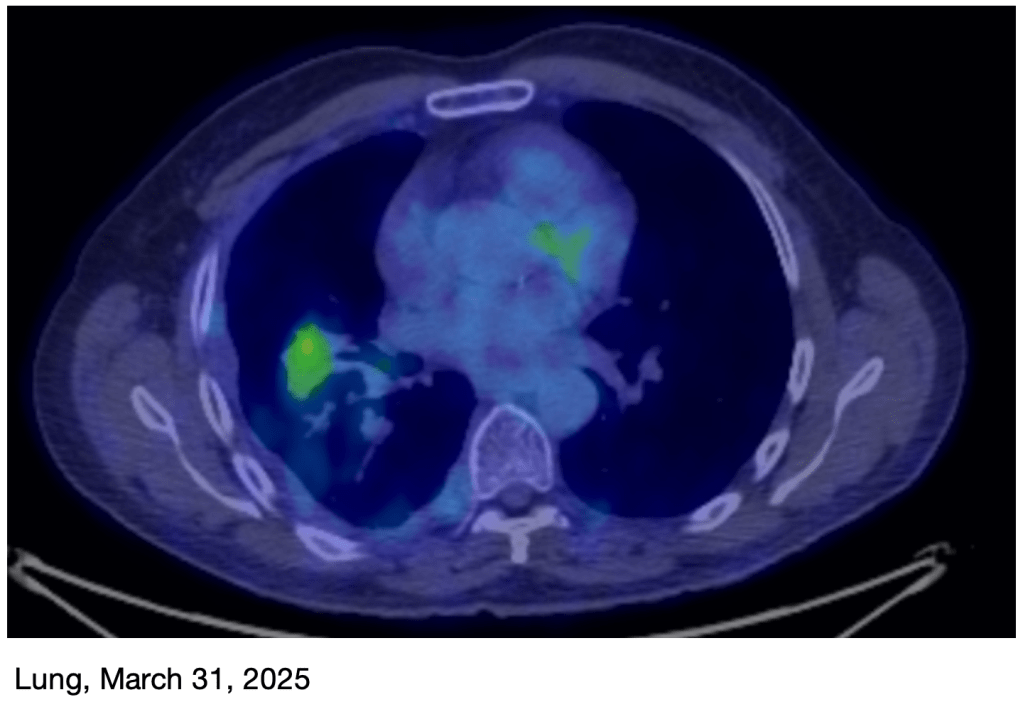

March PET Scan: I just had a new PET scan on Monday, and the results are great! The tumor on my rib is basically gone, and the primary tumor in my lung is now very small, just a faint reminder of what it was! This is obviously great news! I’ll have another scan in June.